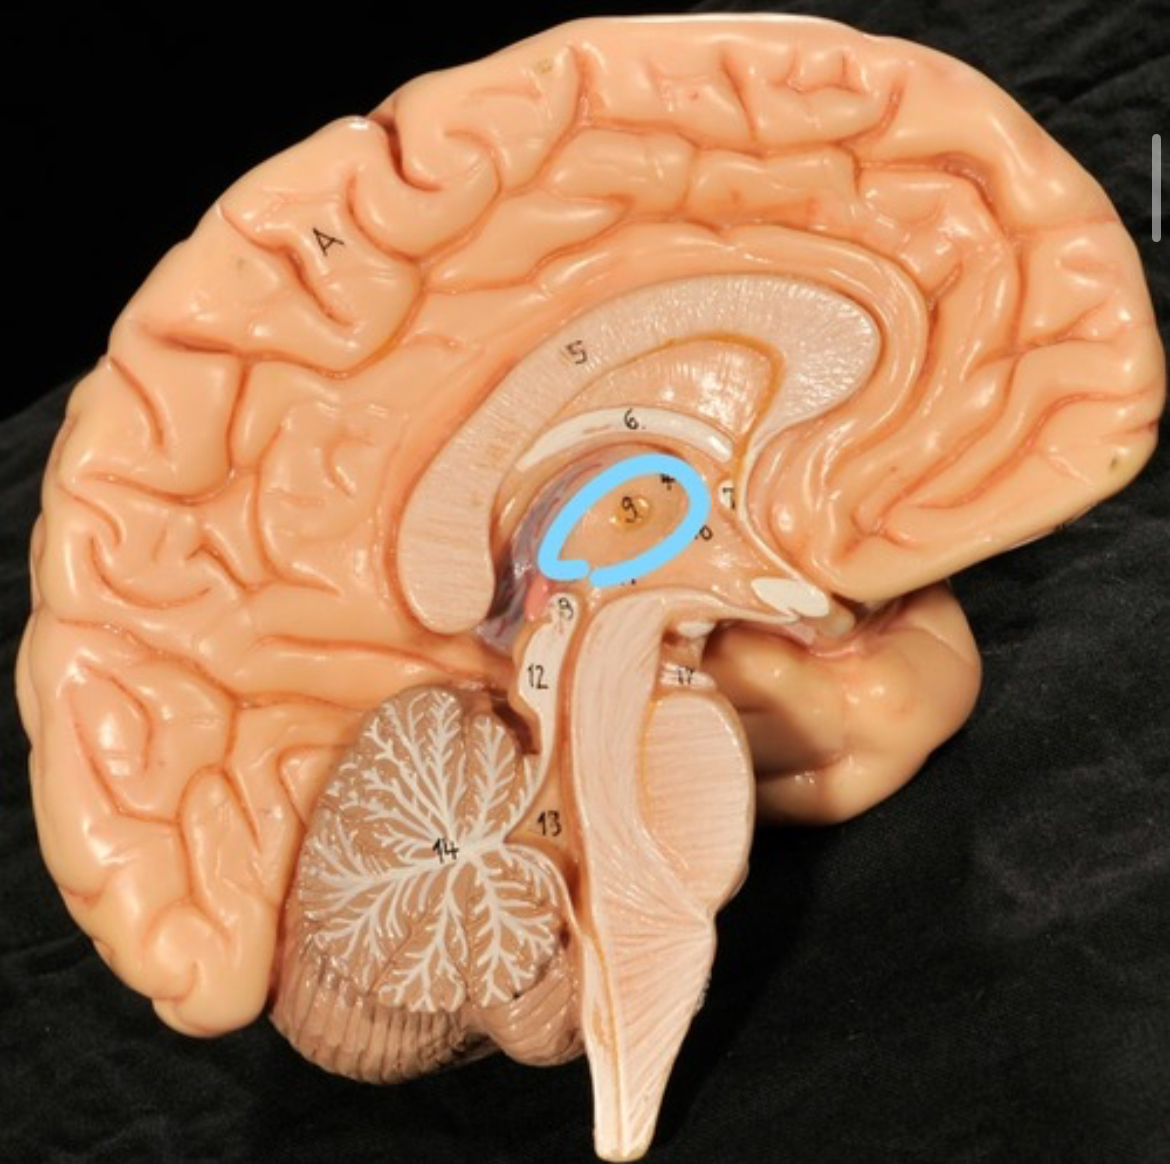

Thalamus

Choroid plexus of 3rd ventricle

Thalamus